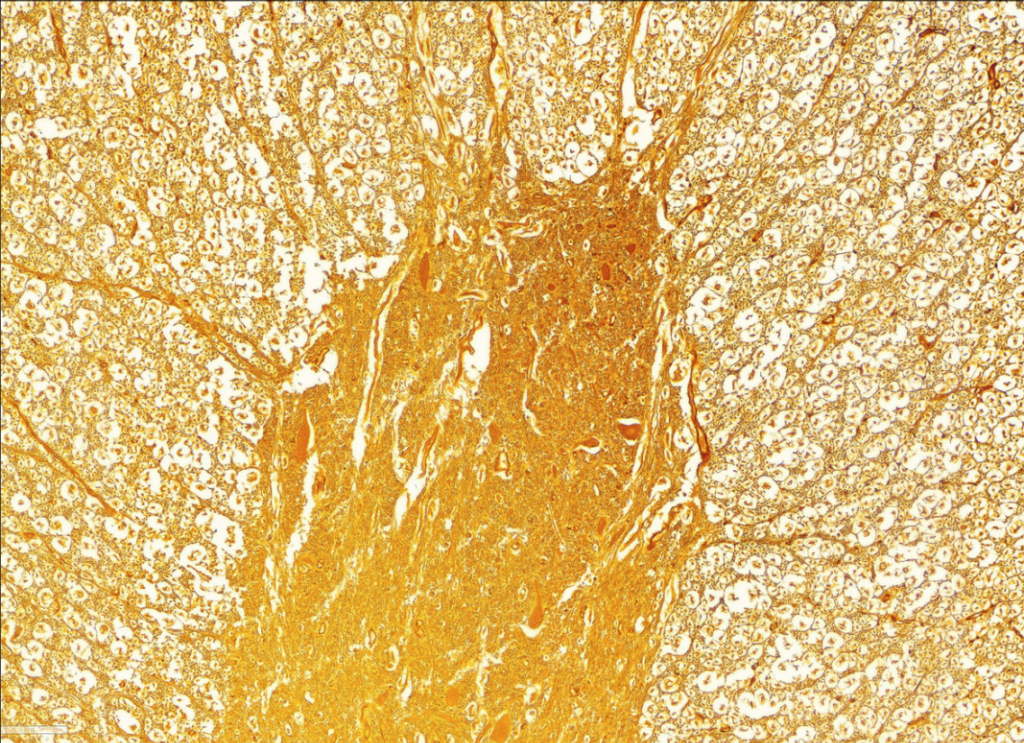

- Istota biała i istota szara (rdzeń kręgowy)